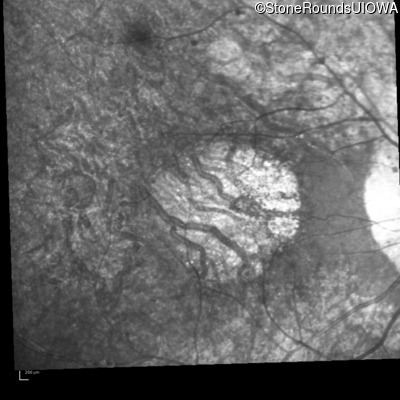

Infrared Fundus Photograph - Right - 20/50

Exemplar